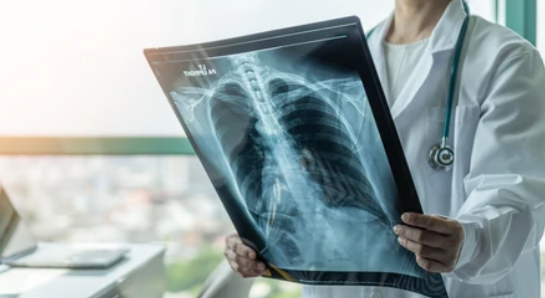

폐암 검사법

폐암을 진단하기 위해 사용되는 다양한 검사법이 있습니다. 폐암의 조기 발견과 정확한 진단을 위해 다음과 같은 주요 폐암 검사법들이 사용됩니다:

1. 폐암검사법- 흉부X선: 폐암검사에서 가장 일반적으로 사용되는 방법 중 하나입니다.

흉부X선은 폐의크기, 모양, 이상부분(결절,종양등)을 시각적으로 확인하는데 도움을 줍니다. 그러나 조기폐암을 발견하기어려울 수 있으므로, 더 정교한 검사가 필요할 수 있습니다.